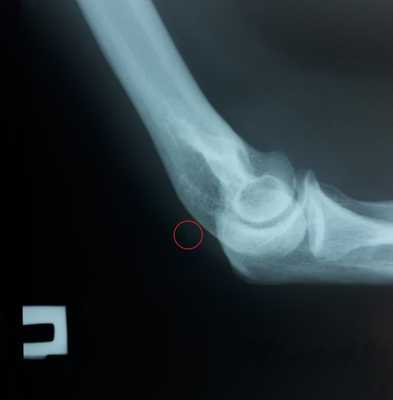

При выполнении рентгенограмм иногда можно увидеть отрыв небольшого костного фрагмента от локтевого отростка.

Рассчитывать на этот признак при диагностике не стоит. Но его наличие следует трактовать как отрыв трицепса и делать МРТ для его исключения.